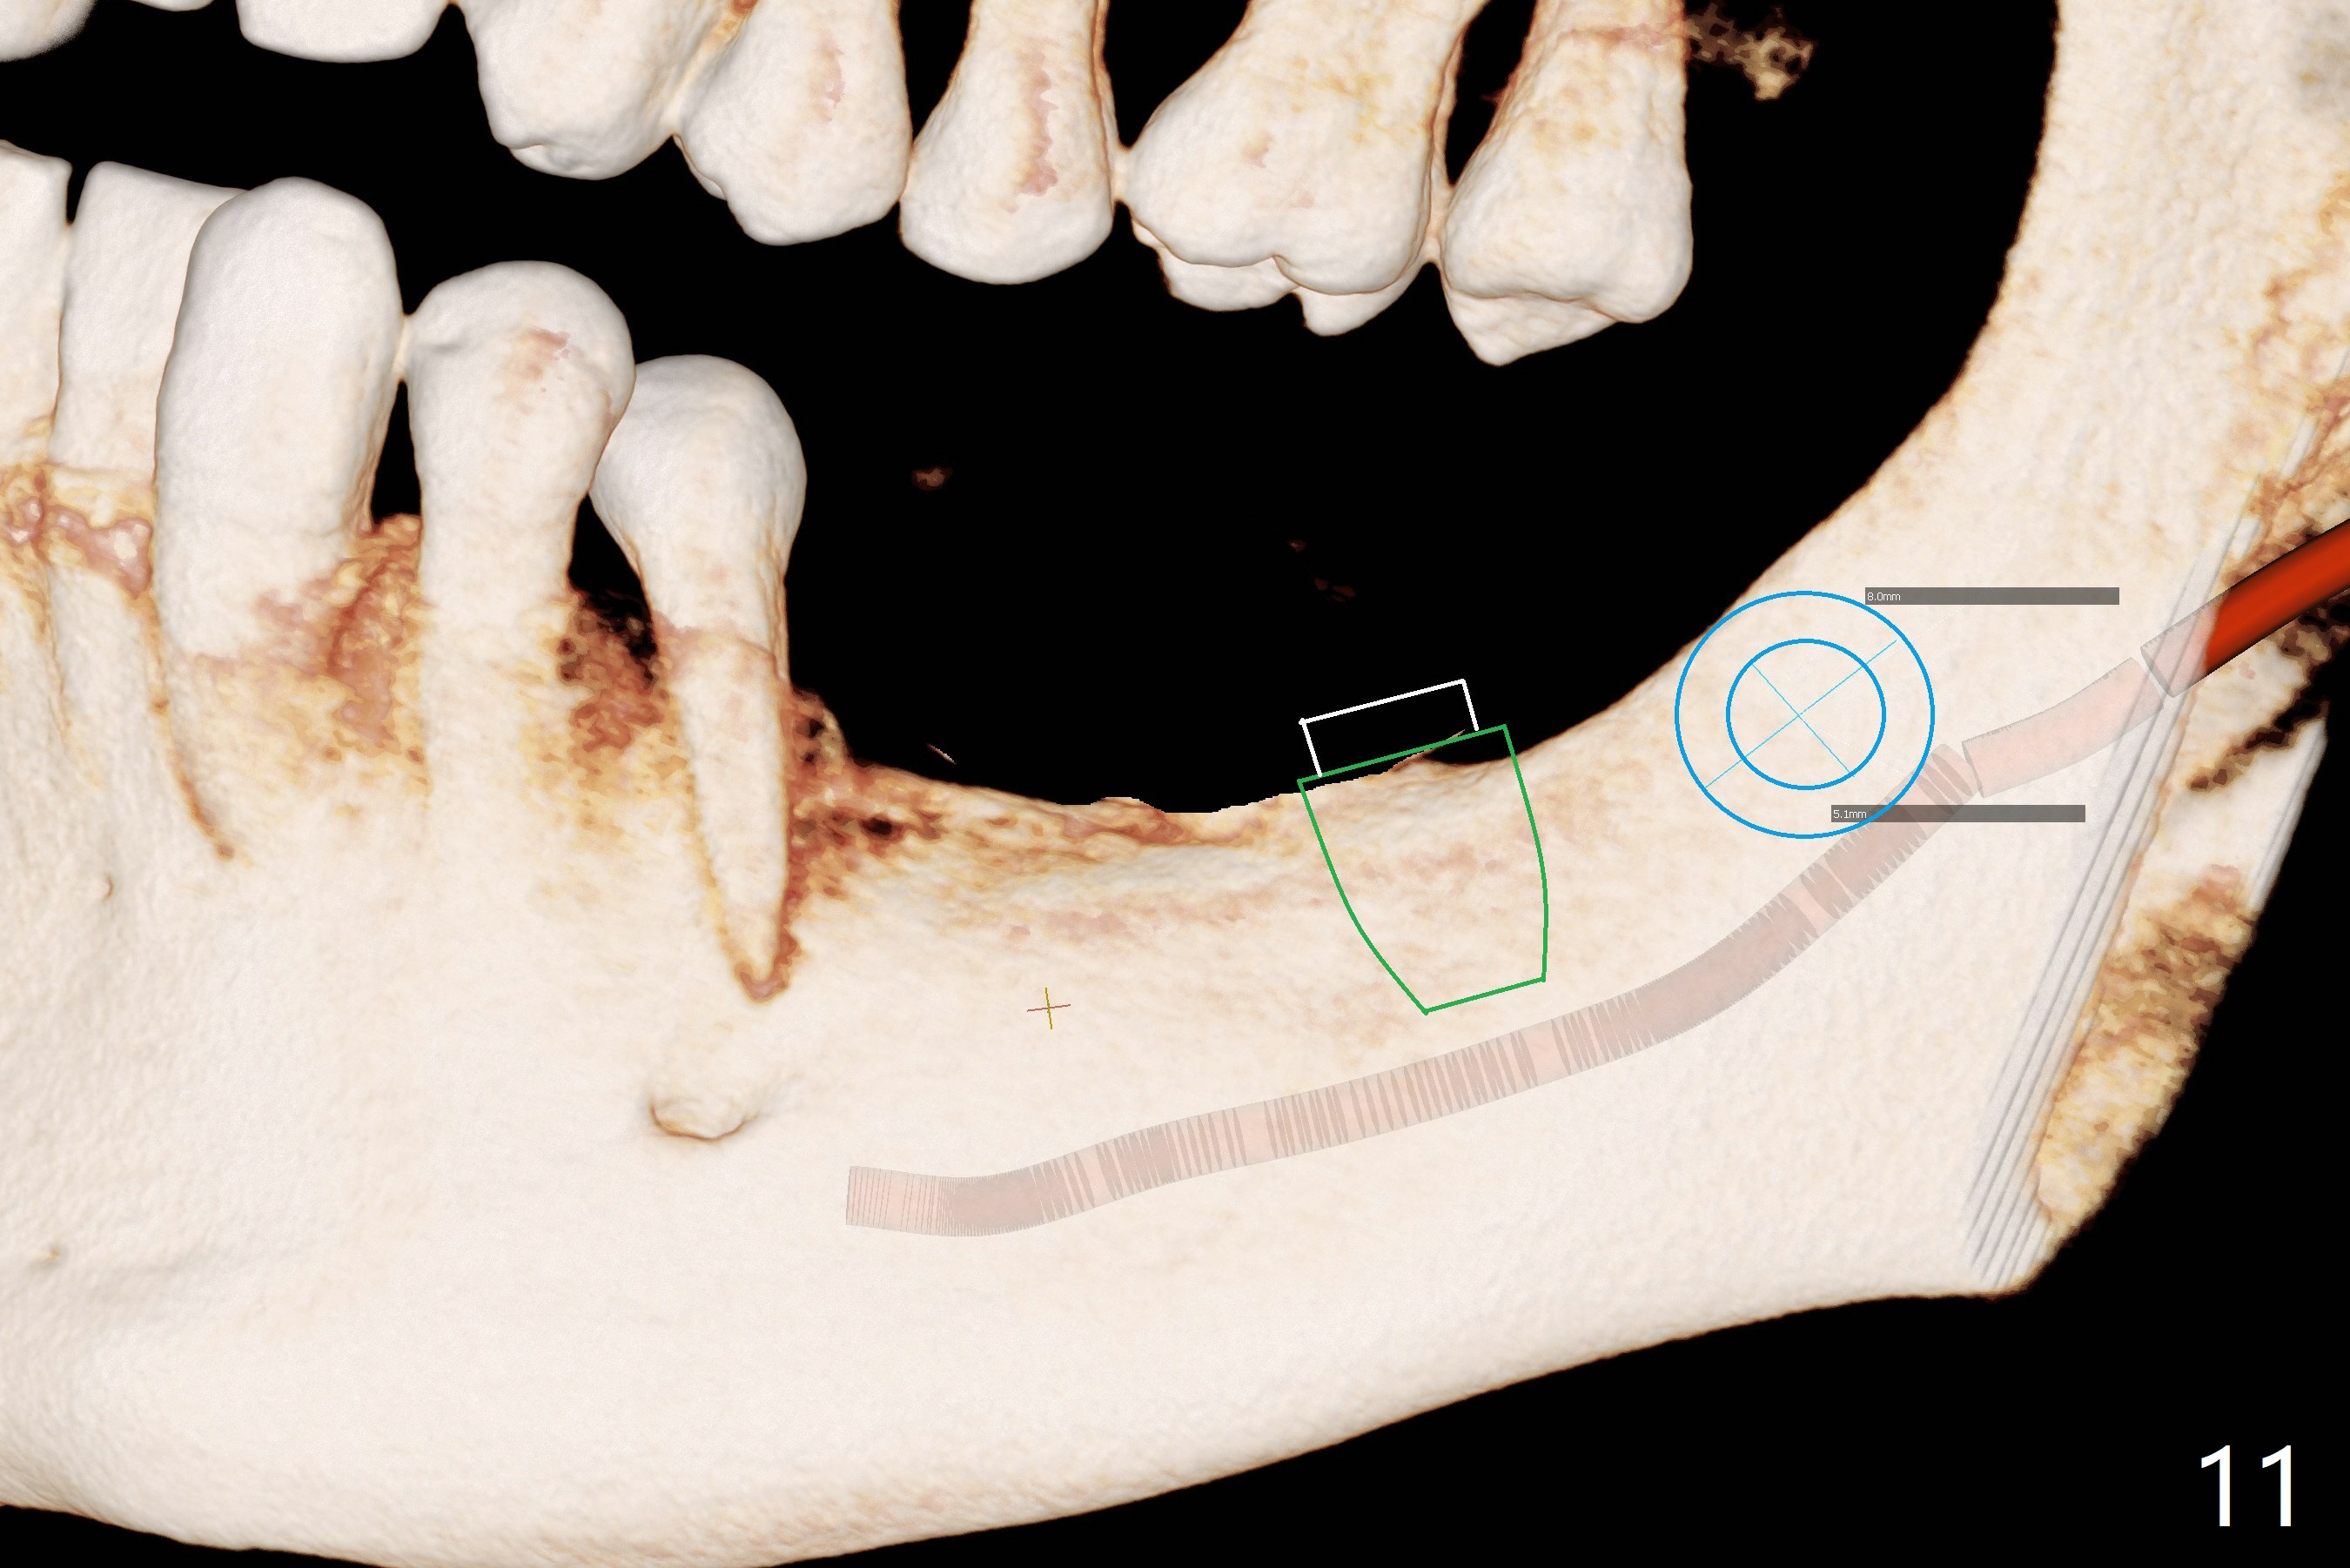

Preop photo shows severe mesial tilt of the tooth #18 (Fig.1). After extraction, the osteotomy is established in the apical end of the socket, where the buccolingual width is limited. It appears that an extra wide implant (5.9 mm) may perforate one of buccolingual plates. On the other hand, the buccal plate (Fig.2 double arrows) is intact and approximately 2 mm tall, whereas the lingual one is thin and lower. Initial osteotomy confirms that bone heights at #18 and 19 are 6 and 8 mm, respectively. Counting 2 mm of the buccal plate and bone graft lingually, a 8 mm long implant may be a practical option at the site of #18. After initial placement of two of 5x8 mm SM implants (Fig.3), the depth of the implant at #19 is adjusted twice (Fig.4,5). With placement of autogenous and allograft (Vanilla, Fig.5 *)) and abutments, a piece of cotton pellet is placed in each abutment well (access, Fig.6 *). Periodontal dressing is applied to the abutment wells for additional retention (Fig.7 *). Due to local poor oral hygiene, splinted provisional is fabricated 4 months postop (Fig.8) in preparation for limited orthodontic uprighting the tooth #20. The patient has pain with mastication at #18 eleven months post cementation (Fig.9). It appears that both of the implants should be removed with immediate replacement and bone graft. Prepare 4 PRF and sticky bone. The new implant will be 5.0 or 5.5x5 mm (Fig.10 green) with 2.3 mm platform (white). A block graft will be harvested from the ipsilateral ramus using 9/8 and 6/5 mm trephine burs for 2-3 mm in depth (Fig.11 blue). The ring graft will be seated around the platform over the implant (Fig.12).